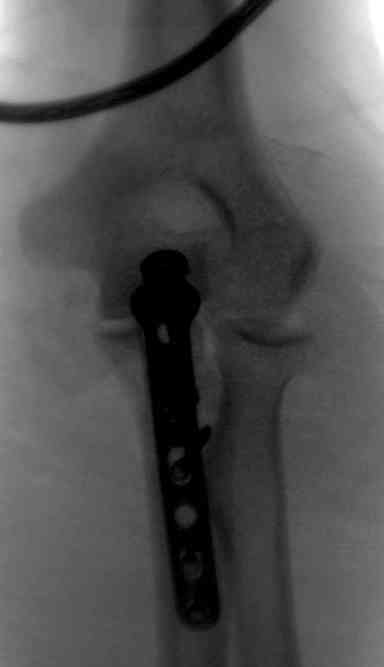

Для фиксации перелома локтевого отростка на сегодня множество преконтурных с блокирующими возможностями пластин.

Стабильную фиксацию, особенно при оскольчатых

переломах, можно добиться, применяя технику Bridge Plate, и за счет тех пластин, где имеется возможность проведения множественных шурупов (2.7 мм) проксимально.

Здесь выставлены несколько случаев и варианты фиксации локтевого отростка, некоторые в комбинации с другими переломами.

1 вариант применен ACUMED локинг пластина

2 вариант